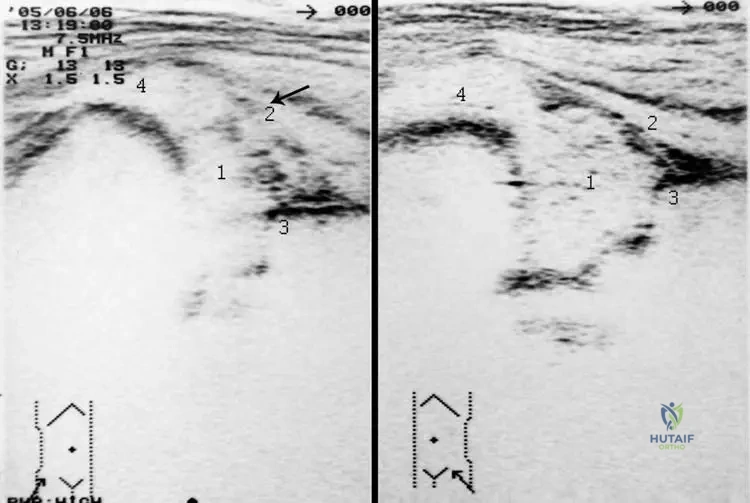

Question 41

Rationale: While the first metatarsophalangeal joint (podagra) is the most common site for acute gout, the clinical context for Fig. 7.4 explicitly shows an "Acute gout spasm of the left knee," indicating that the knee is another frequently affected large joint. The ankle is also a common site, but the image specifically depicts the knee.

A 62-year-old male undergoes arthroscopy for chronic knee pain and suspected inflammatory arthritis. During the procedure, white, chalky deposits are noted within the joint.

Rationale: The clinical context for Fig. 7.5 a, b states, "Deposits of urate crystals may occur in the synovium (a) and in the cartilage of the knee joint (b) as visualized by arthroscopy." This indicates that both these tissues are common sites for urate crystal deposition within the joint. While menisci are cartilaginous structures, the description is more encompassing of the joint's cartilage and synovium.